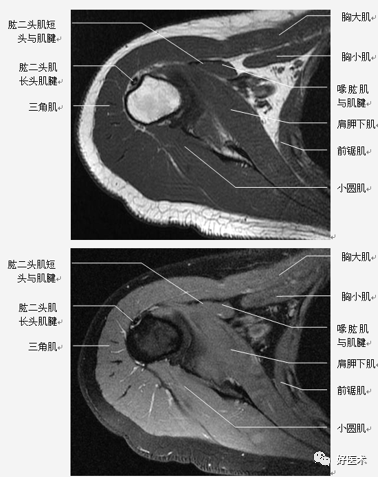

横轴位:取三维立体定位像的冠状像,扫描层面与关节盂垂直,扫描范围从肩峰至肱骨颈下。

-

斜冠状位:取横断位作定位像,扫描层面与冈上肌腱平行,扫描范围为锁骨外端至肩峰。

斜矢状位:取横断位作定位像,扫描层面与关节盂平行,扫描范围包括肱骨头和整个关节盂。

轴位:评估Bankart lesions 和盂唇损伤、评估肩胛下肌肌腱。

斜冠状、斜矢状:显示肩袖及冈上肌走行、显示喙肩弓。

斜冠状、轴位:评估盂唇撕裂、肱二头肌长头腱与上盂唇的连接。

轴位:显示肩胛下肌腱撕裂、盂唇撕裂

冠状位:显示肩袖撕裂、盂唇撕裂

矢状位:显示肩袖撕裂、盂唇撕裂